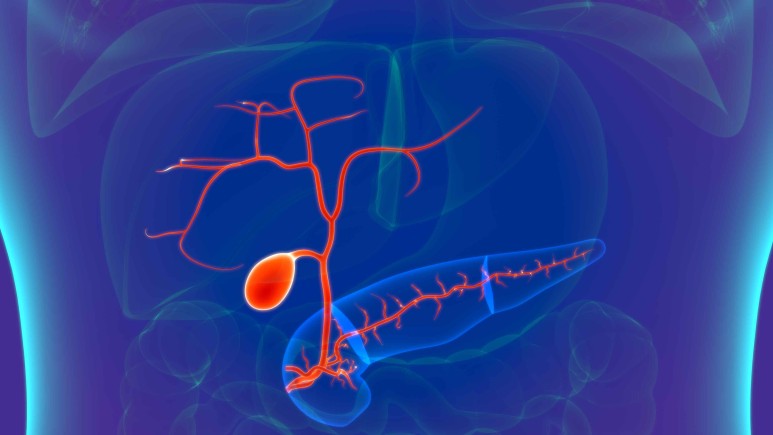

담관이 막혀 담관의 확장이 이루어지는데 처음에는 정상으로 보이는 경우가 있으나 시간이 지나면 문제가 발생합니다.

담관 담석과 양성 협착의 경우 보다 종양으로 인하여 담관이 막힐 경우 담관 확장이 더욱 심해집니다.

이렇게 담관이 확장된 경우에는 배액을 시행하면 담관의 크기가 이전과 같이 정상으로 돌아갑니다.

그러나 담관을 배액하고도 담관 확장이 계속 남아 있는 경우가 있는데 이는 담관 배액시기를 놓쳐 지연되면 발생합니다.

또한 담낭 관원위부의 총 담관이 막히는 경우 담즙의 압력 상승으로 담낭까지 확장될 수 있습니다.